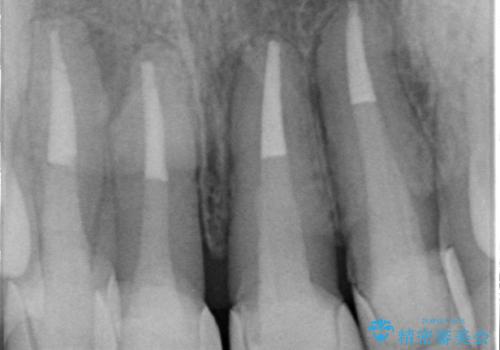

- 20年前に治療した前歯のセラミッククラウンが老朽化し見た目の改善を求めて来院されました。

不十分な根管治療を含めたセラミッククラウンのやりかえ治療を計画します。